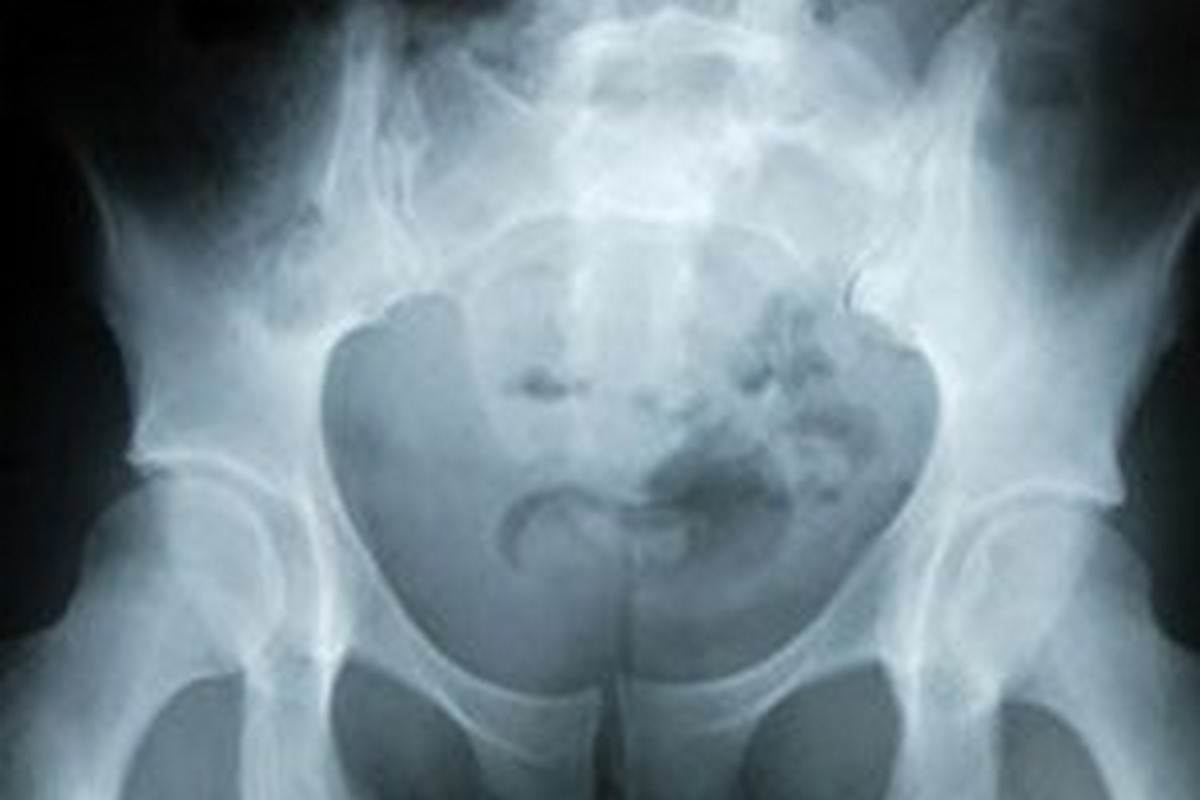

Przepuklina powstaje na skutek nieprawidłowego przemieszczenie się narządów wewnętrznych (np. jelit) poza jamę brzuszną. Może mieć różną postać, z czego najczęściej występująca to przepuklina pachwinowa – dotyka ona 30 proc. mężczyzn. Jedną z przyczyn powstawania przepukliny są osłabione powłoki brzuszne w wyniku postępującej z wiekiem utraty kolagenu, a także brak ruchu, otyłość czy ciężka praca fizyczna.